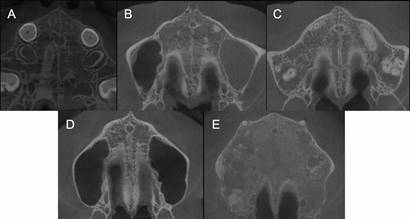

La maduración de la sutura palatina media fue evaluada en el corte axial y clasificada utilizando un método de análisis visual de maduración de Angelieri y cols.8 (Figura 1, Tabla 1), por un examinador ciego y calibrado (T.V.D.), usando un computador con pantalla de alta definición en una habitación oscura. No se realizaron ajustes en el contraste o brillo de estas imágenes. Para la calibración, un radiólogo oral y maxilofacial experto y calibrado (G.C.S.), realizó la clasificación de 10 imágenes de cortes axiales, las cuales luego fueron presentadas al evaluador principal para su clasificación (T.V.D.). Se realizó posteriormente una segunda evaluación a los 10 días, donde las mismas imágenes fueron ordenadas al azar para su clasificación por el evaluador principal (T.V.D.).

Angelieri y cols.8 propusieron una metodología para obtener un corte transversal de la SPM en CBCT y realizar su evaluación morfológica individual en el eje axial, clasificándola en 5 etapas: A, B, C, D y E. Estos autores reportaron una gran variabilidad en la distribución de las etapas de maduración sutural respecto a la edad cronológica. Su estudio incluyó 140 sujetos, con edades desde 5,6 a 58,4 años. En el grupo de 14 - 18 años, un 56% de los sujetos presentó etapas de maduración tempranas compatibles con una EMR no quirúrgica. Sin embargo, los pacientes adultos evaluados fueron agrupados como un solo conjunto (>18 años), impidiendo realizar una evaluación de este grupo específico. Lamentablemente, existe escasa evidencia, con muestras pequeñas y edades muy heterogéneas, sobre el estudio de la representación morfológica individual de la SPM en este grupo etario. Este puede presentar variadas respuestas clínicas frente a EMR, y es precisamente a ellos a quienes se dirige la utilización de anclaje esqueletal (MARPE) para lograr la expansión como opción de tratamiento no quirúrgico6,7. Por esta razón, el objetivo del presente estudio fue evaluar el estado de maduración de la SPM en adolescentes y adultos jóvenes chilenos.